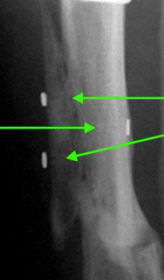

Bridging callus is seen along the line of the olive wires (identified by the remaining washers).